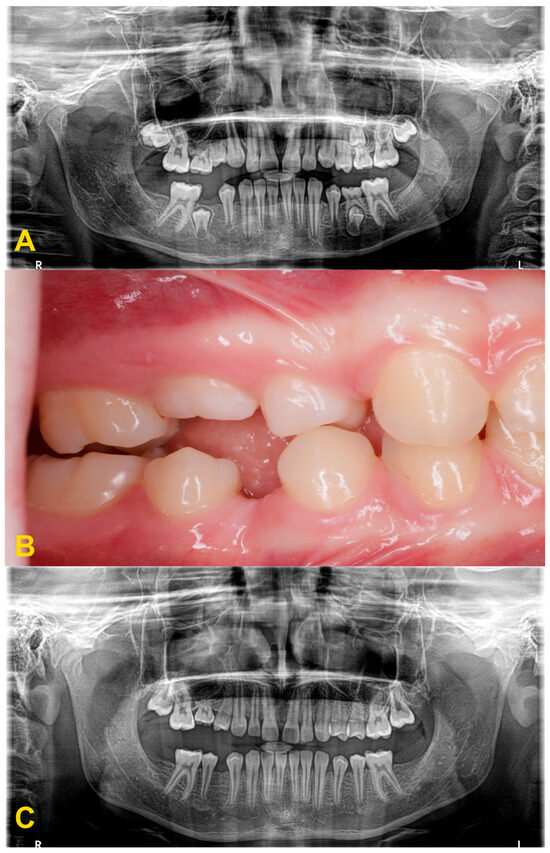

Figure 3.

Panoramic X-ray examinations: (A) mild infraocclusion of tooth no. 55 (immersion of 1–2 mm); (B) moderate infraocclusion of tooth no. 55 (infraposition of 2–3 mm), displacement and growth delay of permanent successor, and angulation of the adjacent teeth with loss of space; and (C) severe infraocclusion of tooth no. 75 (immersion of more than 3 mm), displacement and growth delay of permanent successor, severe angulation of the adjacent teeth with loss of space (the same patient as in Figure 6C).

Intraoral photography: (A) mild reinclusion of tooth no. 85 in the presence of a permanent successor—the patient requires observation; (B) moderate reinclusion of teeth nos. 55 and 85 in the absence of permanent successors, and presence of lateral open bite—the teeth require extraction; (C) severe reinclusion of tooth no. 75 in the presence of permanent successor (the same patient as in Figure 3C)—the tooth requires extraction; and (D) infraocclusion within the permanent dentition—tooth no. 36—the tooth should be removed (the same patient as in Figure 4).

Progression of infraocclusion in tooth no. 55 in the absence of a permanent successor. Extraction is recommended due to the possible progression of the bone defect and inclination of adjacent teeth. Spontaneous exfoliation of tooth no. 75 with infraocclusion and self-correction of second premolar’s distoinclination. Missing teeth nos. 37 and 47. Failure of eruption of teeth nos. 17 and 27, surgical exposure is indicated. (A) panoramic X-ray, (B) intraoral photography, and (C) panoramic X-ray with 4-year follow-up.